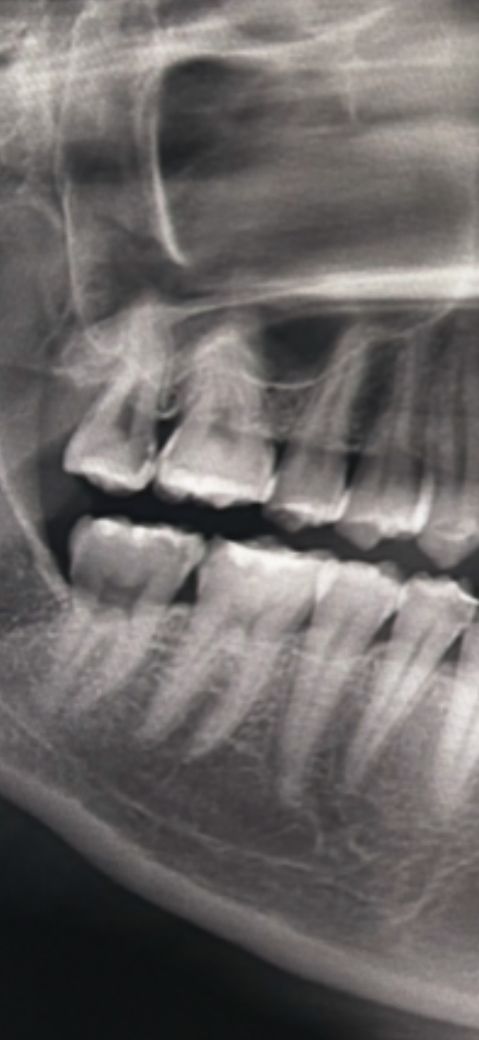

어금니 충치 신경치료를 꼭 해야 할까요?

맨끝 위에 어금니가 충치가 깊은편이라고

신경치료를 해야한다고 하는데 꼭 해야 하나요?

• 1번 째 사진

엑스레이상으로도 이미 충치가 신경에 도달한 것 같습니다 신경치료말고는 치수절단술을 시도해볼 수 있습니다